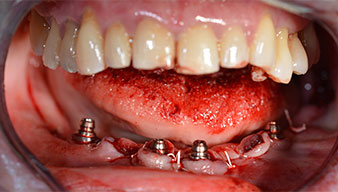

Para la planificación y la minimización del riesgo, se realizó una tomografía volumétrica tridimensional (TVD, Planmeca) que mostró que la calidad y la cantidad del tejido óseo era suficiente para la intervención quirúrgica y el tratamiento inmediato con el método Fast & Fixed. Siguiendo el protocolo de este método, se insertaron los implantes en la región de las piezas 35, 32, 42 y 45. Debido a la inclinación de hasta 45 grados de los implantes distales, el perfil de emergencia se desplazó hacia posterior y se generó un mayor polígono de soporte (fig. 3).

método Fast & Fixed

Fig. 3

Tras la extracción de la dentición residual en el maxilar inferior, se realizó la incisión crestal en la región comprendida entre la pieza dental 37 y la 47.

A continuación, se identificó el agujero mentoniano (foramen mentale) como la estructura anatómica límite y se alisó el cortical de la cresta ósea con la pieza de mano recta y una fresa redonda grande (fig. 4).